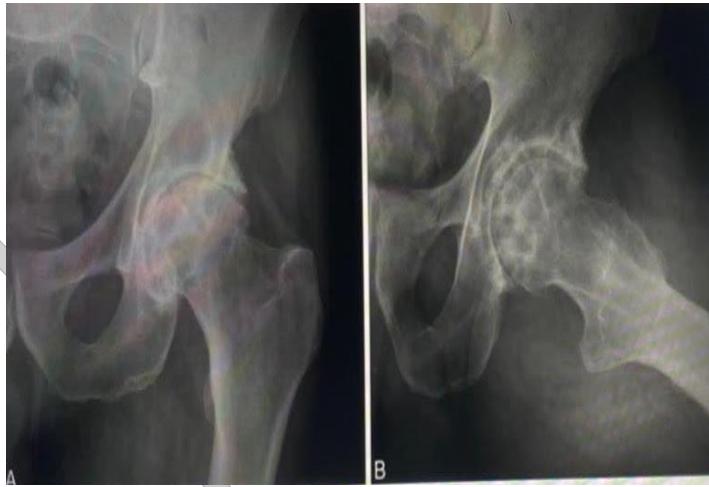

Examination of HIP

https://www.youtube.com/watch?v=Hkqr3mg6IWQ&pp=ygUUSGlwIEV4YW1pbmF0aW9uIE9TQ0U%3D

https://www.youtube.com/watch?v=R9IiCO9QjPY&pp=ygUUSGlwIEV4YW1pbmF0aW9uIE9TQ0U%3D

Station 3: Hip Examination

Hip Examination

Case B: Pelvic Trauma

4.1) Open Book Fracture Management

1. Diagnosis? Answer: Open book fracture

2. Initial management? Answer: ATLS protocol, pelvic binder application

3. Mention 3 complications: Answer:

- Bleeding

- Pelvic instability

- Neurological injuries

4. Difference between stable and unstable management:

Stable open book fractures can typically be managed non-operatively, with the use of a pelvic binder or external fixation to stabilize the anterior pelvic ring until the injury heals.

Unstable open book fractures require surgical intervention to achieve anatomic reduction and stabilization of both the anterior and posterior pelvic rings.